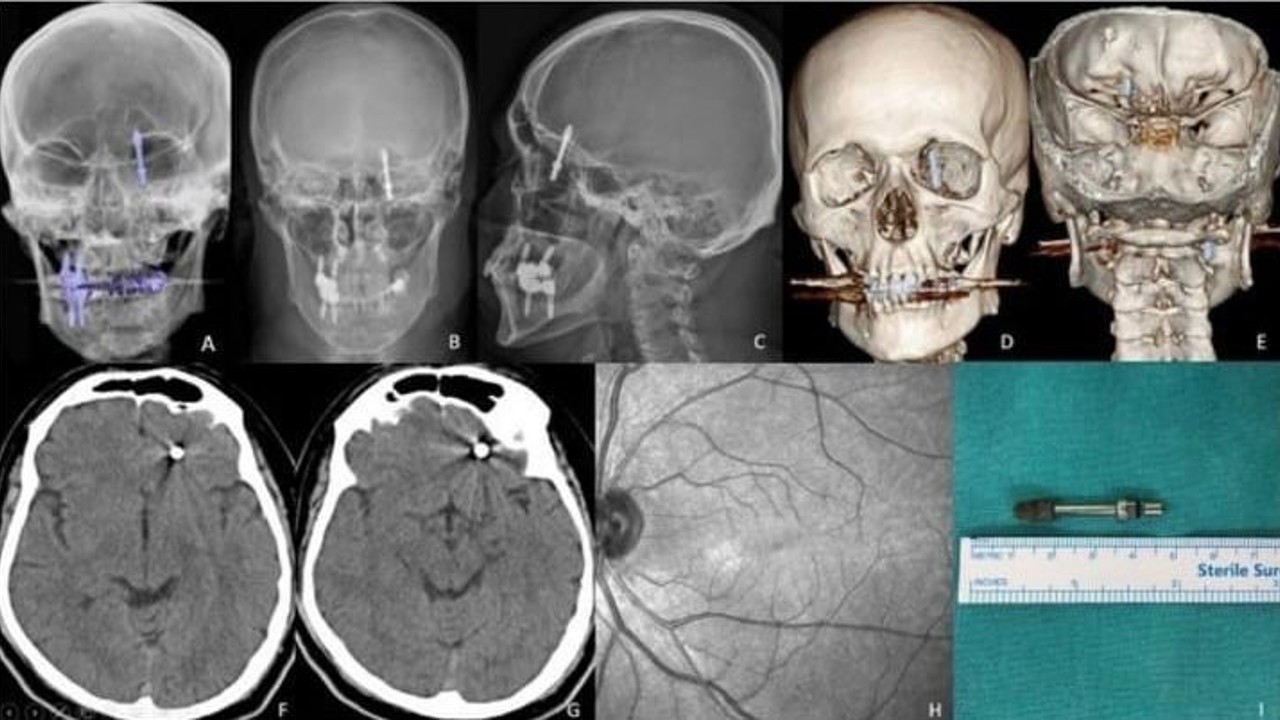

BURSA (İHA) – Bursa’da diş tedavisi için gittiği özel klinikte yaptırdığı implant işlemi, fabrika işçisi Ramazan Yılmaz’ın (40) hayatını kabusa çevirdi. İddiaya göre, doktorun hatalı müdahalesi sonucu implant vidası çene kemiğini delip kafatasına saplandı. Ölümle burun buruna gelen talihsiz adam, saatler süren ameliyatla hayata tutundu. Ancak aradan geçen 2 yıla rağmen ne adalet yerini buldu, ne de sorumlular cezalandırıldı. Hatalı bulunan diş hekimine ise sadece 10 muayene ücreti ceza verildi.

Nilüfer ilçesinde özel bir diş kliniğinde muayene olan Yılmaz’a, dişlerinin sallandığı gerekçesiyle implant tedavisi önerildi. Ancak iddiaya göre, doktor A.D.’nin hatalı müdahalesi sonucu implant vidası çene kemiğini delip kafatasına saplandı.

Baygınlık geçiren Yılmaz, kliniğin kendi aracıyla hastaneye kaldırıldı. Tomografi çekiminde vidanın beynine kadar ilerlediği ortaya çıktı. Acil ameliyata alınan talihsiz adam, saatler süren operasyonla ölümden döndü.